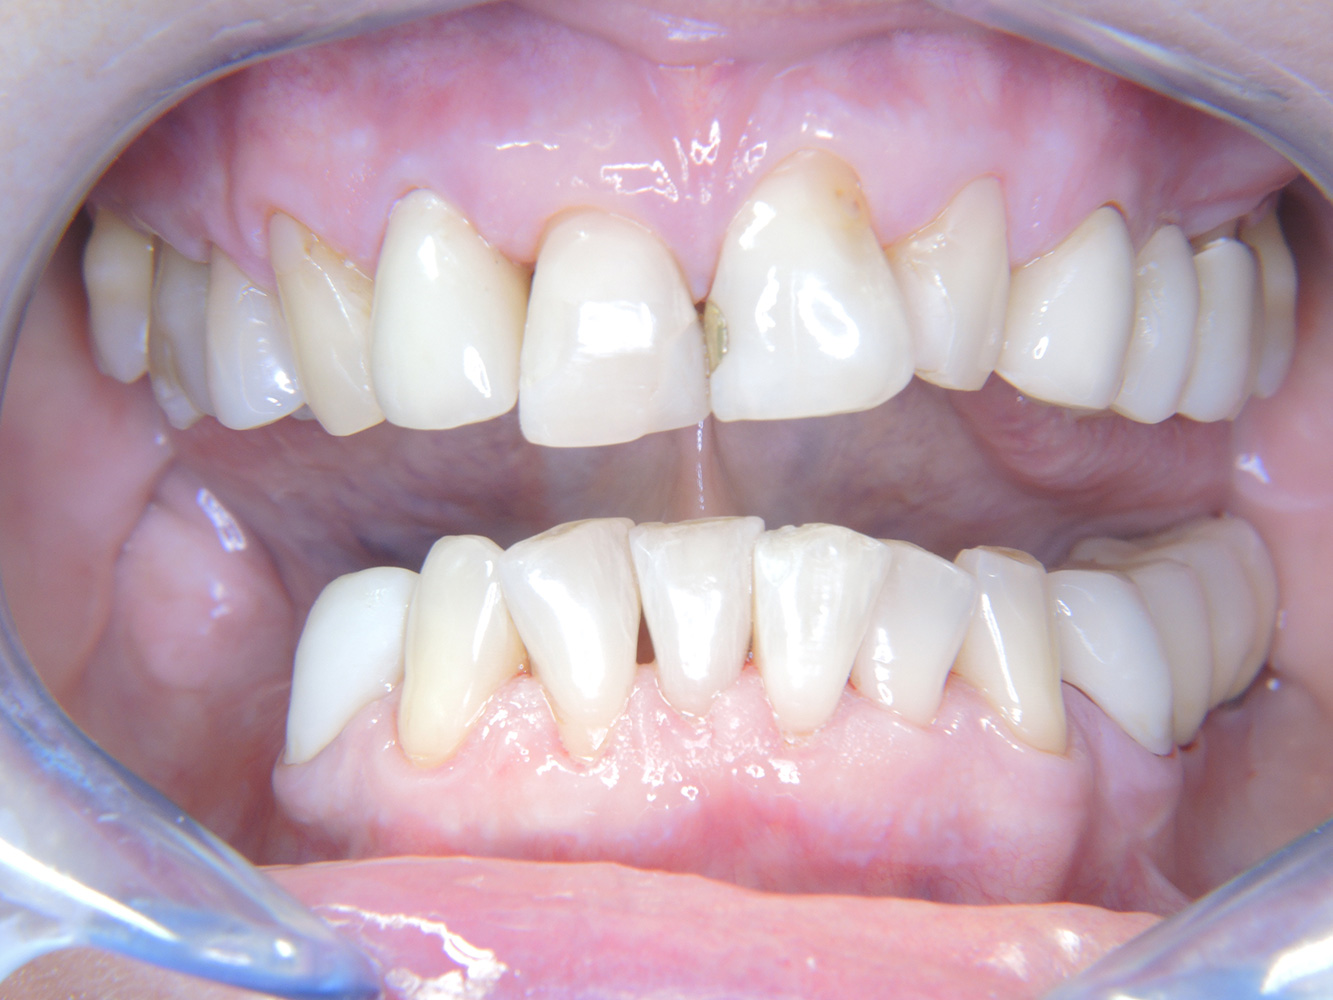

La paciente de 68 años no tiene enfermedades previas relevantes de la salud general ni toma medicación; sus hábitos alimentarios tampoco suponen un riesgo especial. La paciente tiene dos implantes (tercer cuadrante, desde hace cinco años) y una enfermedad previa periodontal (periodontitis en etapa IV, grado B) con pérdida dental. Actualmente las condiciones periodontales son estables, pero la periodontitis aumenta de manera determinante las complicaciones biológicas cuando se realizan implantes y puede ocasionar la pérdida de un implante (21). Para la sesión de profilaxis se hacen cuatro recomendaciones.

Dado que la paciente no tiene factores de riesgo especiales con efectos específicos para los dientes, las necesidades determinadas a partir de la salud oral son determinantes. Se recomienda un estado periodontal detallado una vez al año. De esta forma, es posible responder a la posible progresión de la enfermedad periodontal previa o al desarrollo de periimplantitis a tiempo.

Aunque las condiciones sean estables, no debe descuidarse la motivación y la formación de esta paciente. Hay que prestar especial atención a que aprenda a cómo cuidar los implantes correctamente. Aquí en particular, un buen mantenimiento en casa puede jugar un papel importante en la estabilización a largo plazo de la salud oral y del implante.

Al seleccionar el instrumental, se aplica un procedimiento especial en la zona de los implantes. Para conservar la superficie del implante y, al mismo tiempo, limpiarla con eficacia, es crucial seleccionar los instrumentos y los polvos adecuados, como el uso dirigido de aeropulidores con puntas Paro especiales. La elección de los polvos adecuados puede hacerse según las necesidades y los riesgos, por ejemplo, además del grado apropiado de abrasión, pueden tenerse en cuenta los requisitos alimenticios (como que sean sin azúcar o bajos en sal).

Debido a la situación del implante con la enfermedad periodontal previa, la paciente tiene riesgo de desarrollar periimplantitis; se recomienda un intervalo de recuperación de tres a cuatro meses.